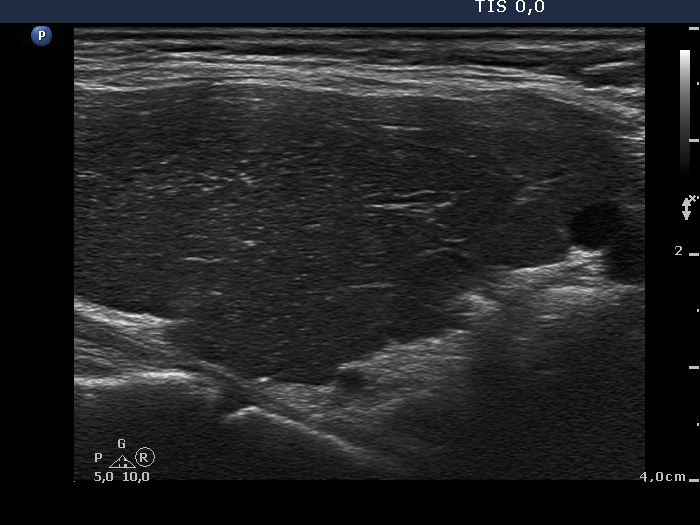

Consecutively operated patients with autoimmune thyroid disease - case 24 (790) (ultrasonographic picture 6)

Lower part of the left lobe, longitudinal view. This pattern is very edifying. There are numerous bright echogenic foci. These are presentations of connective tissue because of the synchronous presence of echogenic lines. Naturally, in this case the presence of echogenic granules does not cause any differential diagnostic problem. However, a similar presentation of echogenic punctate foci in the event of a nodule is not infrequently misinterpreted as microcalcification.